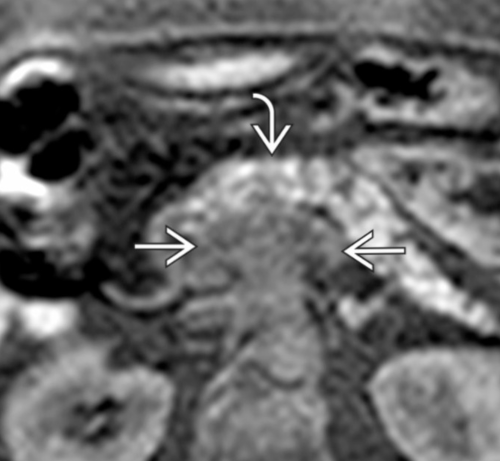

- Infiltration artérielle: <180° vs >180° et cranio-caudalement >2cm vs <2cm

- Infiltration veineuse: Contact, engainement, sténose, occlusion

- Infiltration de la lame rétroporte (entre l’AMS et l’uncus)

Lame rétroporte